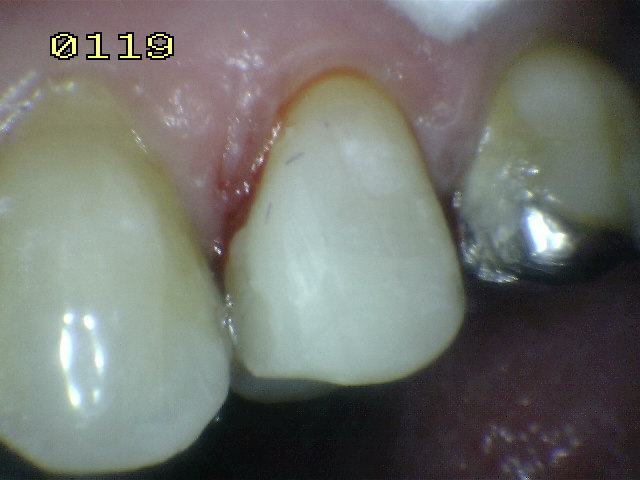

| Pieza

dental 25 para realizar tratamiento de conducto por

necrosis |

Hecho el

tratamiento de conducto, se elimina la totalidad de la

amalgama |

Se bajan en altura las

cúspide palatina, para evitar una futura fractura en

tallo verde. |